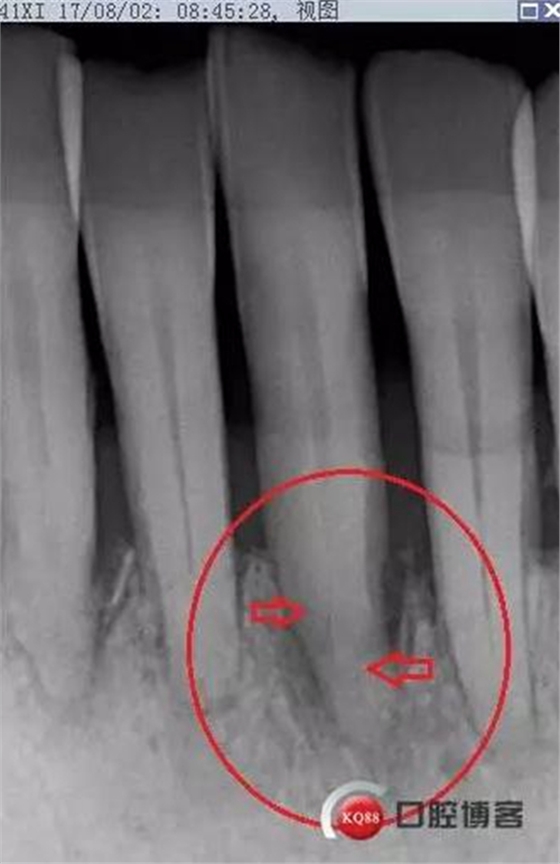

X線(xiàn)示牙槽骨吸收,下頜前牙區(qū)可見(jiàn)齦下牙石影像,牙槽骨吸收至根尖1/3,根周透射影像。

X線(xiàn)示根周透射影骨密度增高。

事后再次查看術(shù)前片,可以看到兩個(gè)根管影像,忽略了。